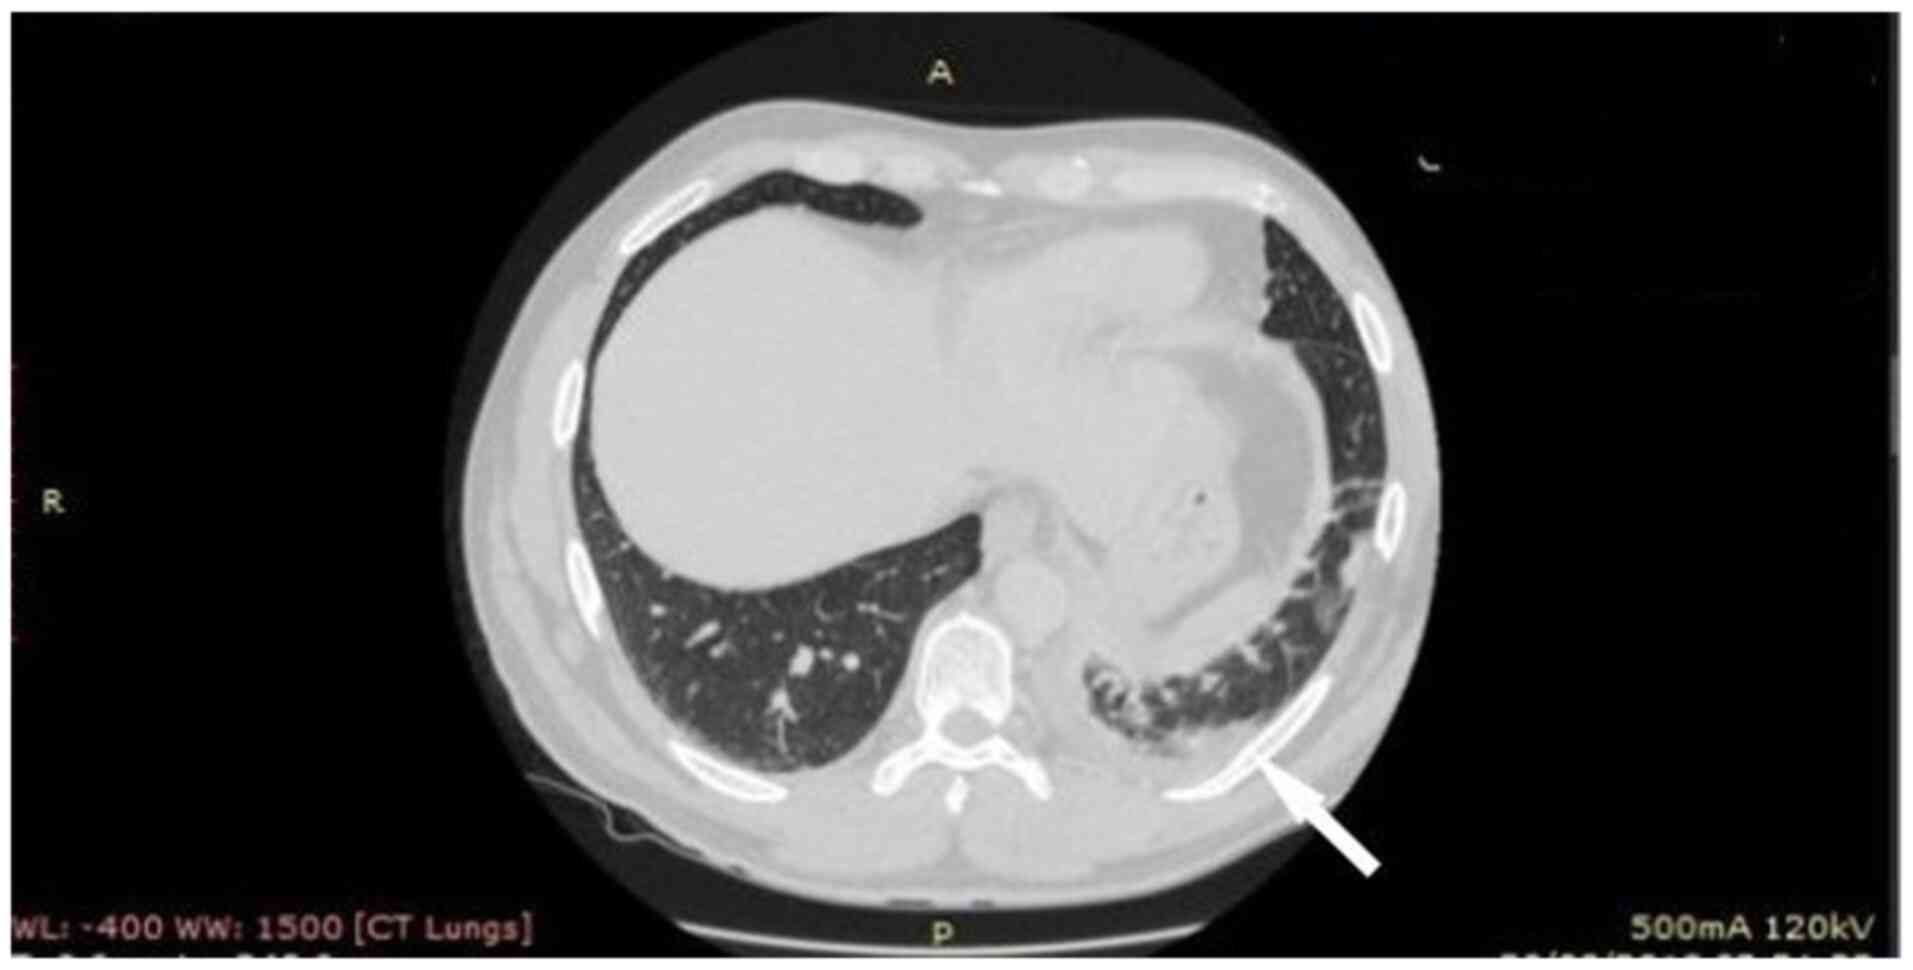

The patient underwent computed tomography (CT) of the chest showing consolidation in the left lower lobe with left pleural effusion, edema of the soft tissue adjacent to the first sternocostal joint and heterogeneity, and invasion of the retrosternal fat (Figs. 2 and 3). In addition, the patient underwent magnetic resonance imaging (MRI) of the chest, to obtain detailed information regarding the pleura and mediastinum, that revealed abnormal soft tissue with dimensions at transverse level 7.0x1.3 cm, containing cystic lesions, adjacent to the first sternocostal joint, indicating inflammation in sternocostal cartilage. MRI also revealed contrast enhancement of the ipsilateral mediastinal pleura, imaging compatible with mediastinitis (Fig. 4).

Figure 3

Lung window: Consolidation in the left lower lobe with left pleural effusion. A, anterior; P, posterior.

The patient presented with improvement in clinical manifestations and blood inflammatory indices on the second day of hospitalization, and the fever subsided on the fourth day of hospitalization. There was no need for surgical procedure due to the good clinical response to antibiotics. The patient received intravenous vancomycin for 4 weeks and then there was a switch to oral treatment with ciprofloxacin 500 mg twice daily for 2 weeks. Table I shows the prescription history and recovery flow of the patient. There was also complete recovery observed in the imaging evaluation (Fig. 5).

Figure 5

Chest computed tomography after 6 weeks of treatment (A) Chest computed tomography (mediastinal window). (B) Chest computed tomography (lung window). Complete remission of the lesions can be seen in both the panels.